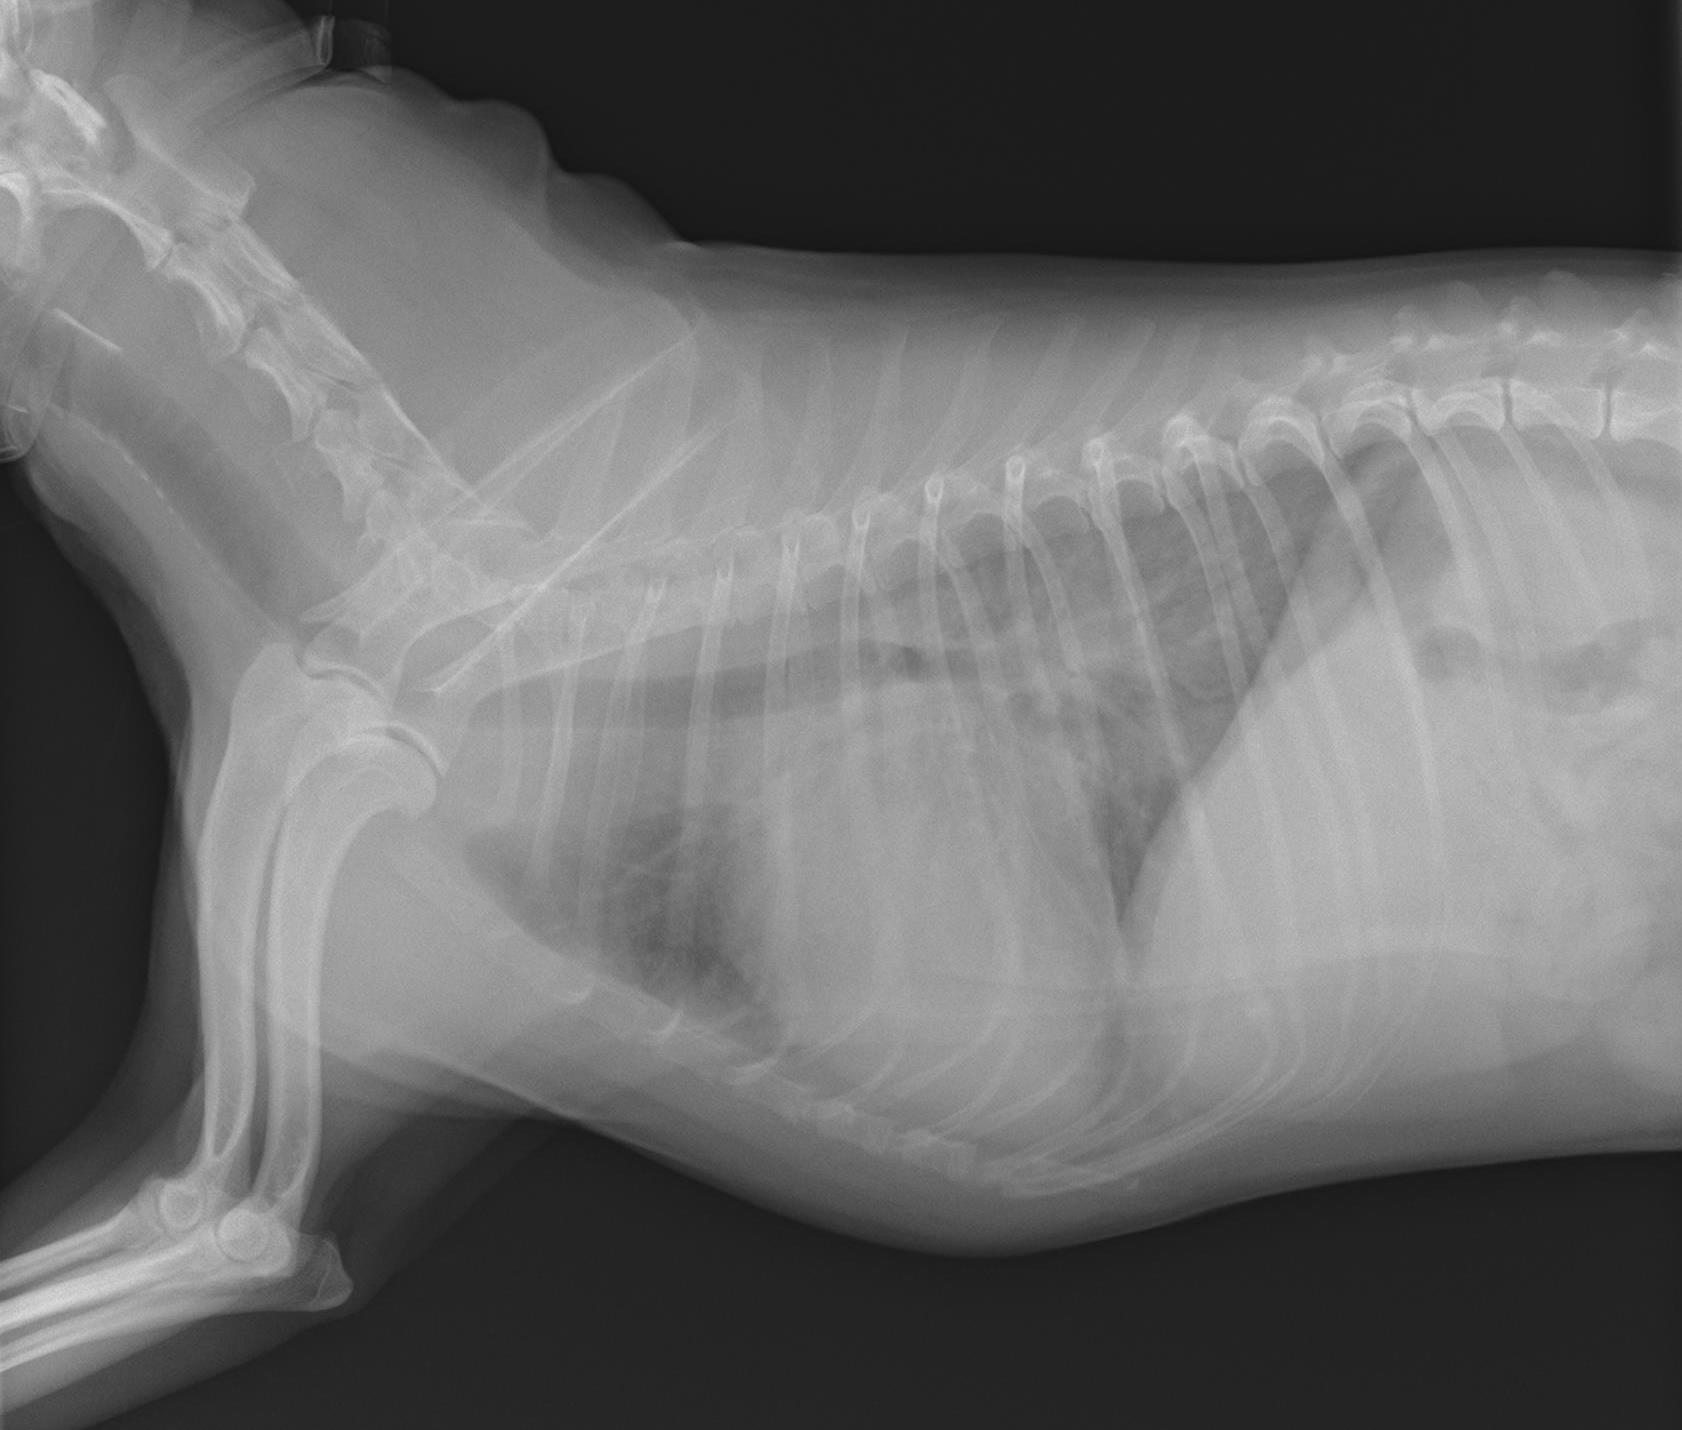

犬の心臓病について。 レイクサイド動物病院|静岡県浜松市にある犬猫専門の動物病院|

心臓の検査 市川市・浦安市の動物病院『ALL動物病院行徳』皮膚科/眼科